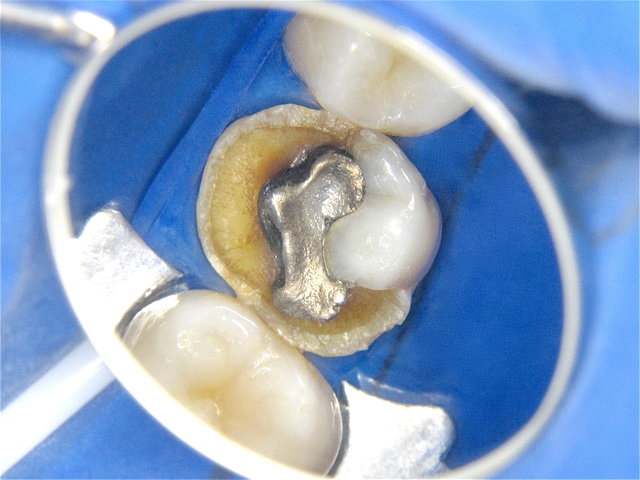

Randspalten in undichter Amalgam-Füllung ...

Composit-Füllung by CLINICDENT ✓